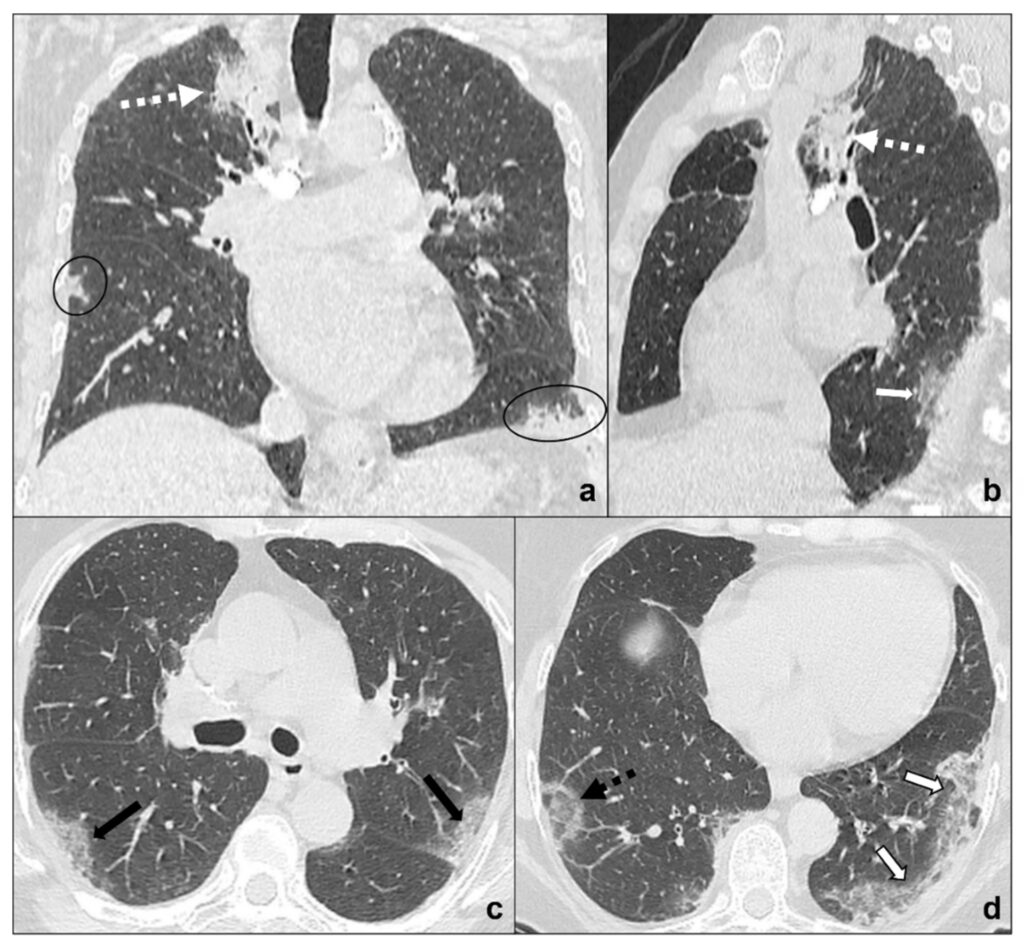

Mistanke om lungekræft opstår ofte efter et røntgenbillede eller en CT-scanning af brystkassen, der viser en plet eller en knude (nodulus) i lungen. Det er vigtigt at bemærke, at de fleste pletter på lungerne ikke er kræft. For at stille en endelig diagnose er en biopsi (vævsprøve) nødvendig. Her udtages et lille stykke væv fra det mistænkelige område, som derefter undersøges under et mikroskop for at se, om der er kræftceller til stede. Yderligere scanninger som PET-scanninger kan bruges til at afgøre, om kræften har spredt sig.